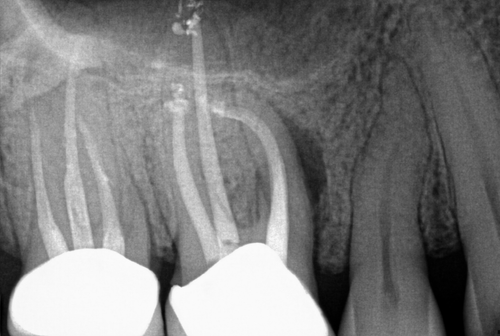

Successful Root Amputation

Resorption

Resorption is a condition where the tooth’s structure starts to break down, either from the inside out or from the outside in. It can be caused by trauma, inflammation, or other factors. Endodontic treatment for resorption involves removing the damaged tissue and reinforcing the tooth with materials that help prevent further damage. The aim is to save the tooth and maintain its functionality as much as possible.